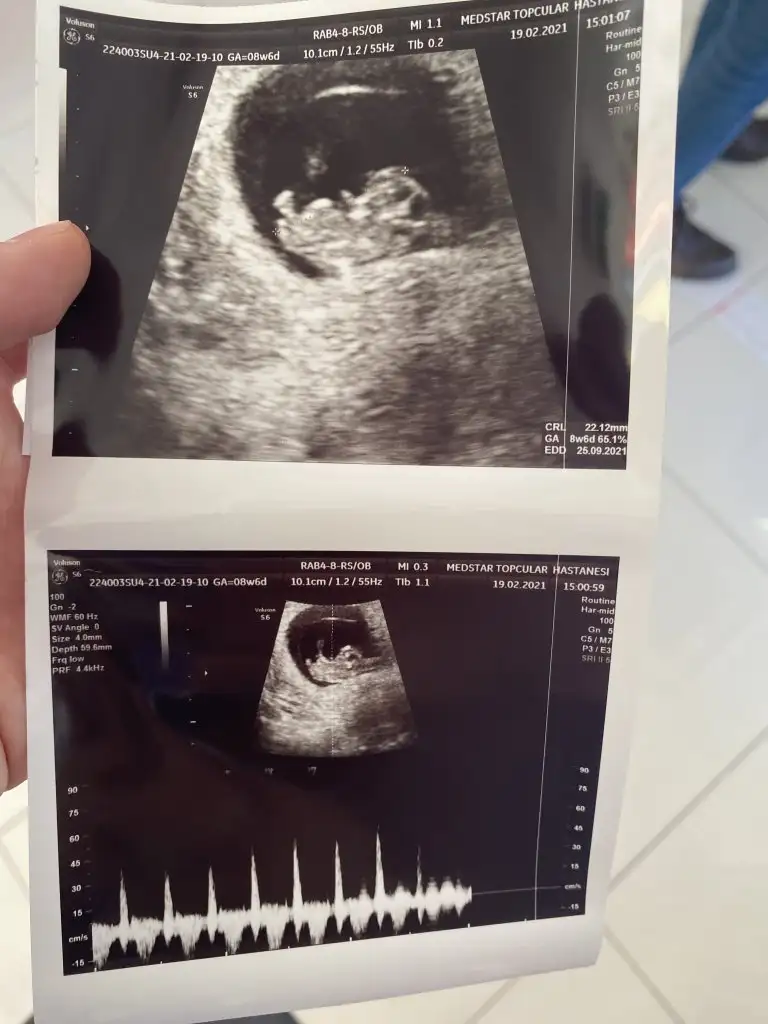

Bundan bahsetmiyorum. Bir sonrakinde kesin konuşacağı sözlerden bahsediyorum.“Açısından emin olamadım kız gibi ama erkeğe de benziyor %65 erkek olabilir ama net değil” doktorumun kurduğu cümle![]()